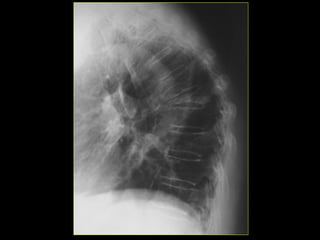

∗ Fractura patológica.

∗ Causa local (carcinoma

metastásico), suelen

ocurrir a nivel de los

cuerpos vertebrales, 1/3

proximal del fémur y ½

proximal del húmero.

∗ Causa generalizada

(osteoporosis senil), con

afectación fundamental en

los cuerpos vertebrales

dorsales y lumbares, así

como el cuello del fémur.